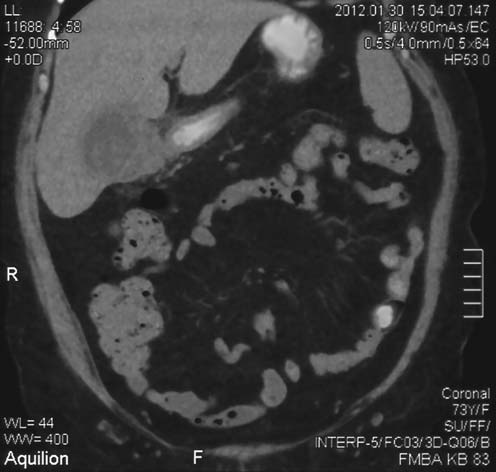

При УЗИ органов брюшной полости (17.01) желчный пузырь в инфильтрате, в области шейки фиксированный конкремент, неравномерное утолщение стенок желчного пузыря. Весь просвет пузыря заполняют множественные конкременты. Признаки диффузных изменений паренхимы печени и поджелудочной железы. Жидкости, увеличенных лимфоузлов в воротах печени нет. Заключение: ЖКБ, острый холецистит, инфильтрат желчного пузыря (рис. 1).

Рис. 1. Желчный пузырь в инфильтрате, с неравномерно утолщенными стенками, в области шейки фиксированный конкремент.